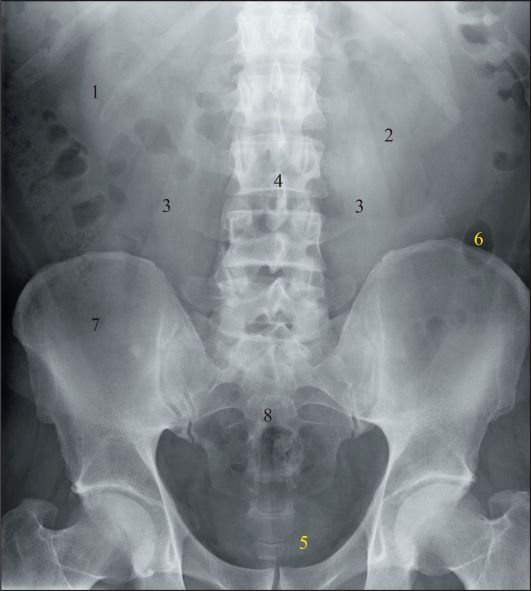

Нормы обзорной рентгенографии брюшной полости